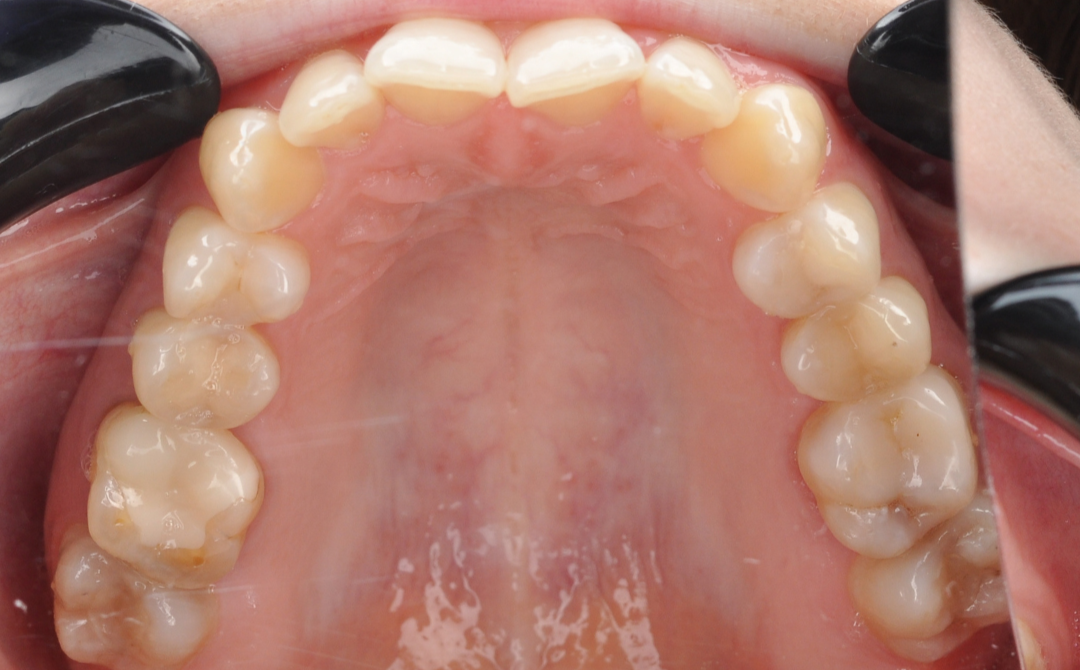

До